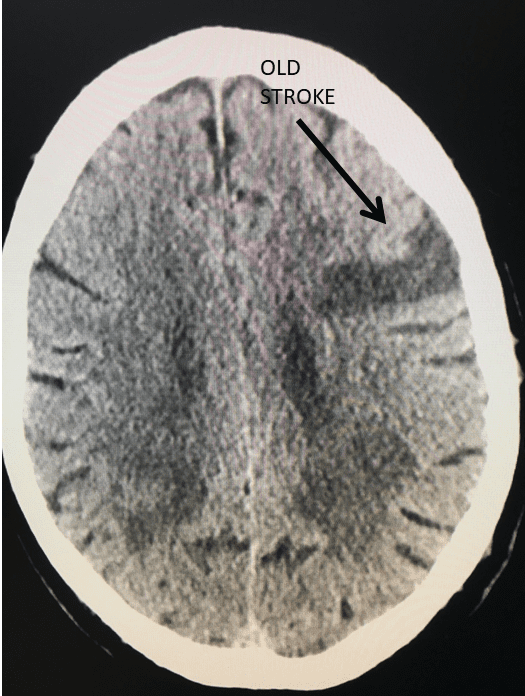

This 77-year-old man with a history of stroke in 2013 presented to a small community hospital with aphasia upon awakening. Given the unclear timing of onset […]